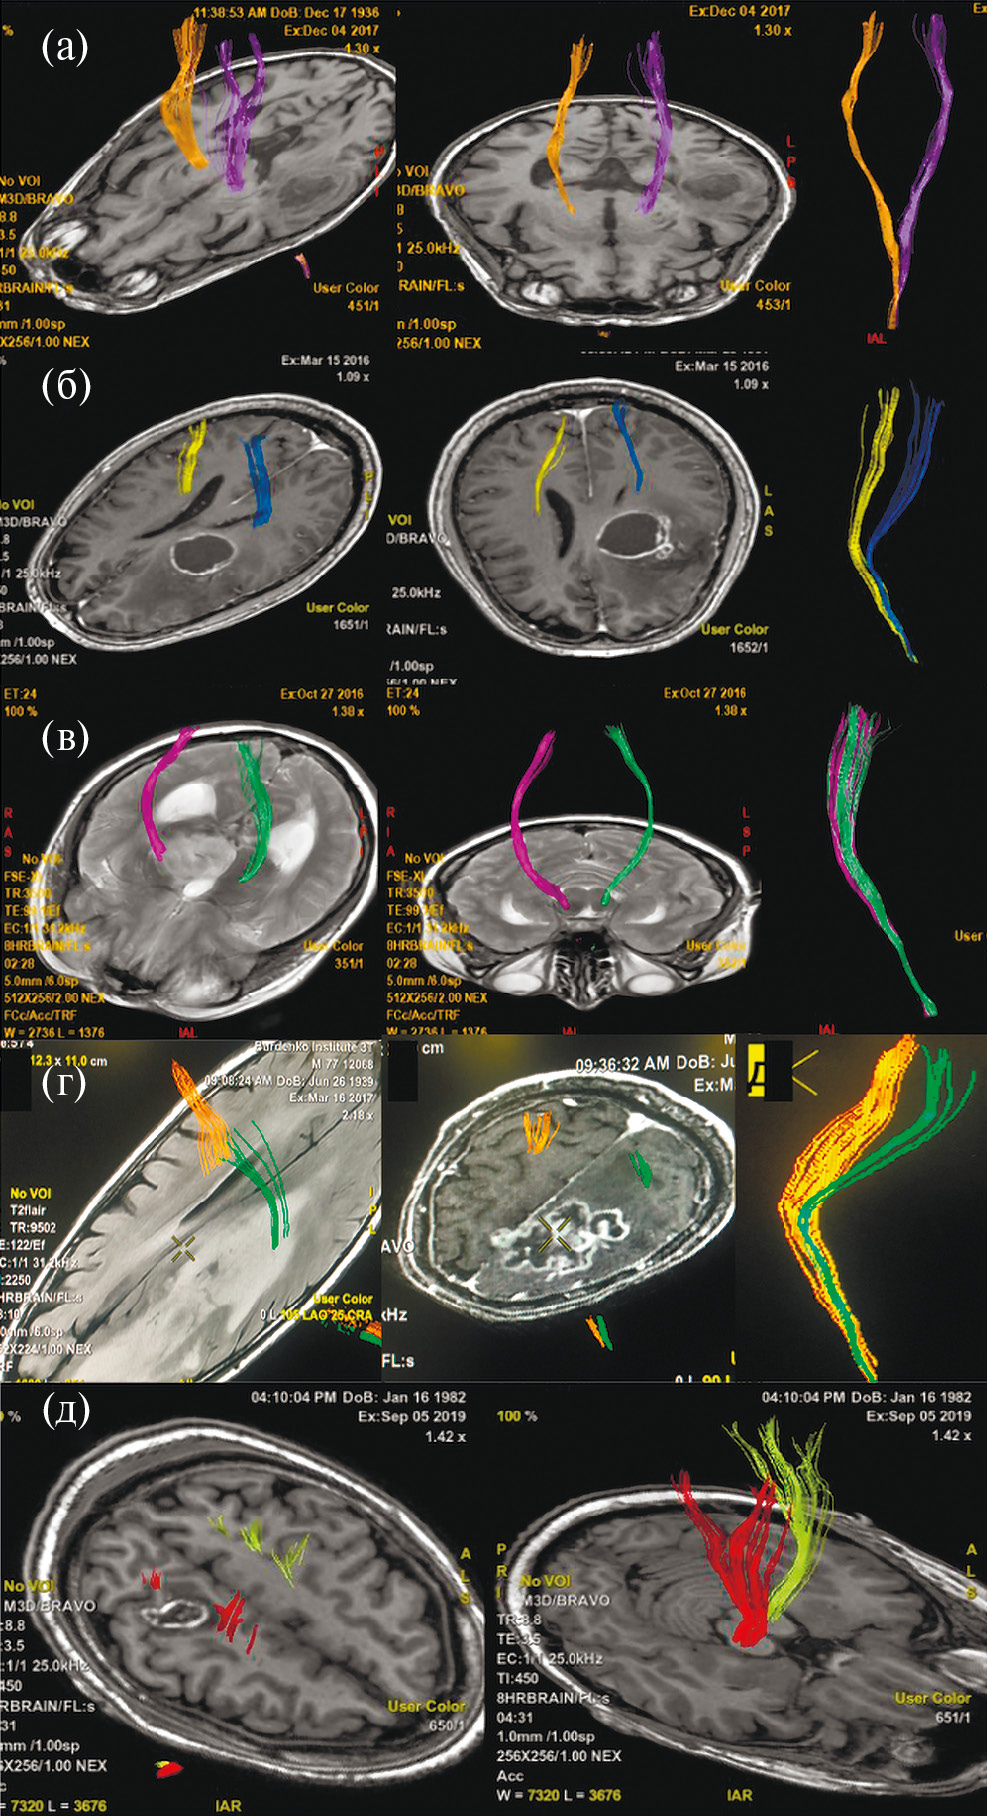

Аласенс (препарат 5-аминолевуленовой кислоты) вводился перорально за 2 ч до разреза ТМО из расчета 20 мг/кг. Из исследования были исключены 12 пациентов, у которых не отмечалось визуальной флуоресценции во время операции. Всем пациентам была проведена оценка мышечной силы до операции, на первые и седьмые сутки после хирургического лечения, выполнена предоперационная МРТ (Т1, Т2, Т2-FLAIR, DWI, T1+C, DTI) с определением расстояния от опухоли до КСТ и типа взаимоотношения между трактом и новообразованием. Было показано, что из 108 пациентов у 21 (19.4%) наблюдался интактный КСТ, у 43 (39.8%) – смещенный, у 34 (31.5%) – смещенный и инфильтрированный, у 8 (7.4%) – инфильтрированный, и только в одном наблюдении опухоль располагалась в структуре тракта, расщепляя его (рис. 1).

Рис. 1. (а) – пример интактного КСТ по данным ДТ-трактографии у пациента с глиобластомой. Тракты симметрично расположены и не отличаются значимо по объему. (б) – пример смещенного КСТ, по данным ДТ-трактографии у пациента с глиобластомой. Тракты не вовлечены в опухоль, однако положение их отличается. (в) – пример инфильрированного КСТ, по данным ДТ-трактографии у пациента с глиомой Grade IV. Несмотря на вовлечение КСТ в опухоль, по данным Т2-FLAIR отмечается правильное, симметричное положение тракта. (г) – пример смещенного и инфильтрированного КСТ, по данным ДТ-трактографии у пациента с глиобластомой. Тракты расположены асимметрично и вовлечены в зону отека-инфильтрации. (д) – пример расщепленного тракта у пациента с анапластической астроцитомой. Опухоль располагается внутри КСТ, расщепляя его волокна.

Fig. 1. Different types of relationship between the corticospinal tract and the tumor according to MR-tractography (intact, displaced, infiltrated, displaced and infiltrated, split).

В литературе вопрос эффективности использования ФМ у пациентов с новообразованиями ФЗЗ прицельно рассматривается лишь в немногих публикациях. Так, в 2019 г. Raffa G. с соавт. было проведено исследование, сравнивающее эффективность комбинированного использования навигационной ТМС, флуоресцентной диагностики (флуоресцин натрия) и нейрофизиологического мониторинга у пациентов с глиомами первичной МК и КСТ. Пациенты, включенные в исследование, были разделены на 2 группы: исследуемую (79 пациентов) и контрольную (55 пациентов). В контрольной группе интраоперационно проводился только нейрофизиологический мониторинг. В исследуемой группе были показаны значимо лучшие результаты как в отношении радикальности операций (тотальное удаление 64.5 против 47.2%, P = 0.04), так и в отношении нарастания мышечной слабости после операции (11.4 vs. 20%) (Raffa et al., 2019). В нашем исследовании статистически значимой разницы в объеме резекции опухоли (как контрастируемой части, так и в режиме Т2-FLAIR) достигнуто не было. Нельзя исключать такие факторы, которые могли повлиять на объем резекции, как больший размер контрастируемой части опухоли в основной группе, наличие объективных причин для остановки резекции в основной группе (24 больных против 8 в контрольной). Возможно, применение ФМ в контрольной группе позволило бы расширить объем резекции у пациентов без объективных причин для остановки резекции. Кроме того, как было показано на выборке из 108 пациентов с использованием МР-трактографии и реконструкции КСТ, опухоль смещает тракт в одну из сторон, локализация опухоли непосредственно в проводящем пучке наблюдается крайне редко (0.9%) (Косырькова, 2021). Таким образом, ФМ может обеспечить максимально радикальное удаление в других направлениях. Lavrador J. P. в своем клиническом наблюдении пациента с новообразованием вблизи КСТ признает эффективность использования ФМ для прицельного забора гистологического материала в условиях ограниченной возможности резекции (Lavrador et al., 2022).

Использование ФМ у пациентов с новообразованиями вблизи моторных зон оправдано, поскольку КСТ в подавляющем количестве случаев располагается в одной стороне от образования и, значит, ограничивает резекцию только в одном из направлений, позволяя в оставшихся достигнуть максимальной радикальности. В нашей серии только в 0.9% случаев образование располагалась в структуре КСТ, расщепляя волокна последнего в разные стороны.